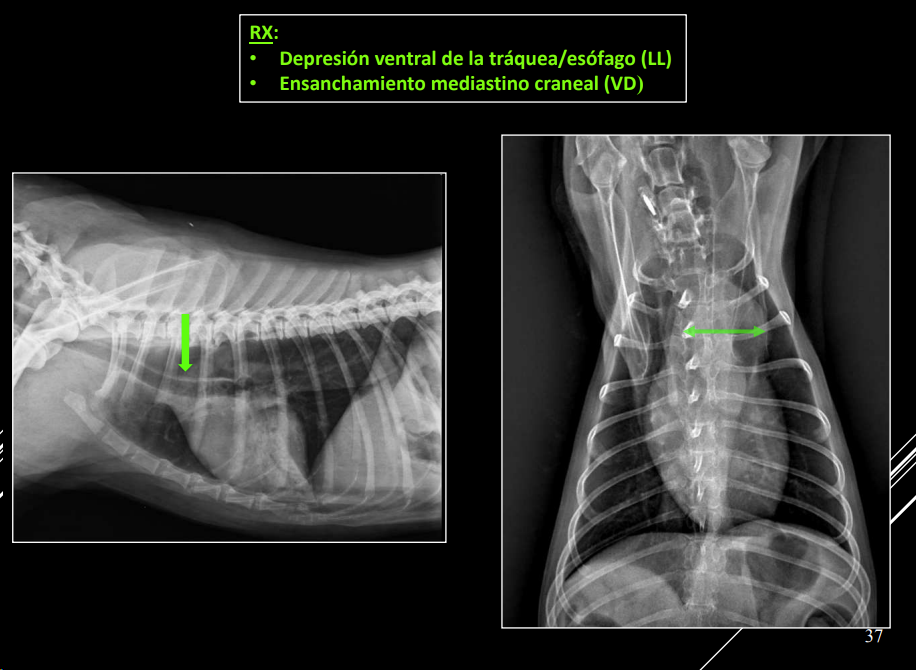

- Desplazamientos (dorsal o ventral).

- Dorsal: cardiomegalia, masa craneoventral.

- Ventral: dilatación esofágica, masa craneodorsal.

Hiliares/Perihiliares: alteraciones esofágicas, tumor base cardiaca, linfoadenopatía traqueobronquial, masa tiroidea ectópica.

-

Masa de opacidad tejido blando que desplaza la traquea y la bifurcación bronquial.

Puede ser por los nodulos parabronquiales, esofagico o por masa en el pulmón